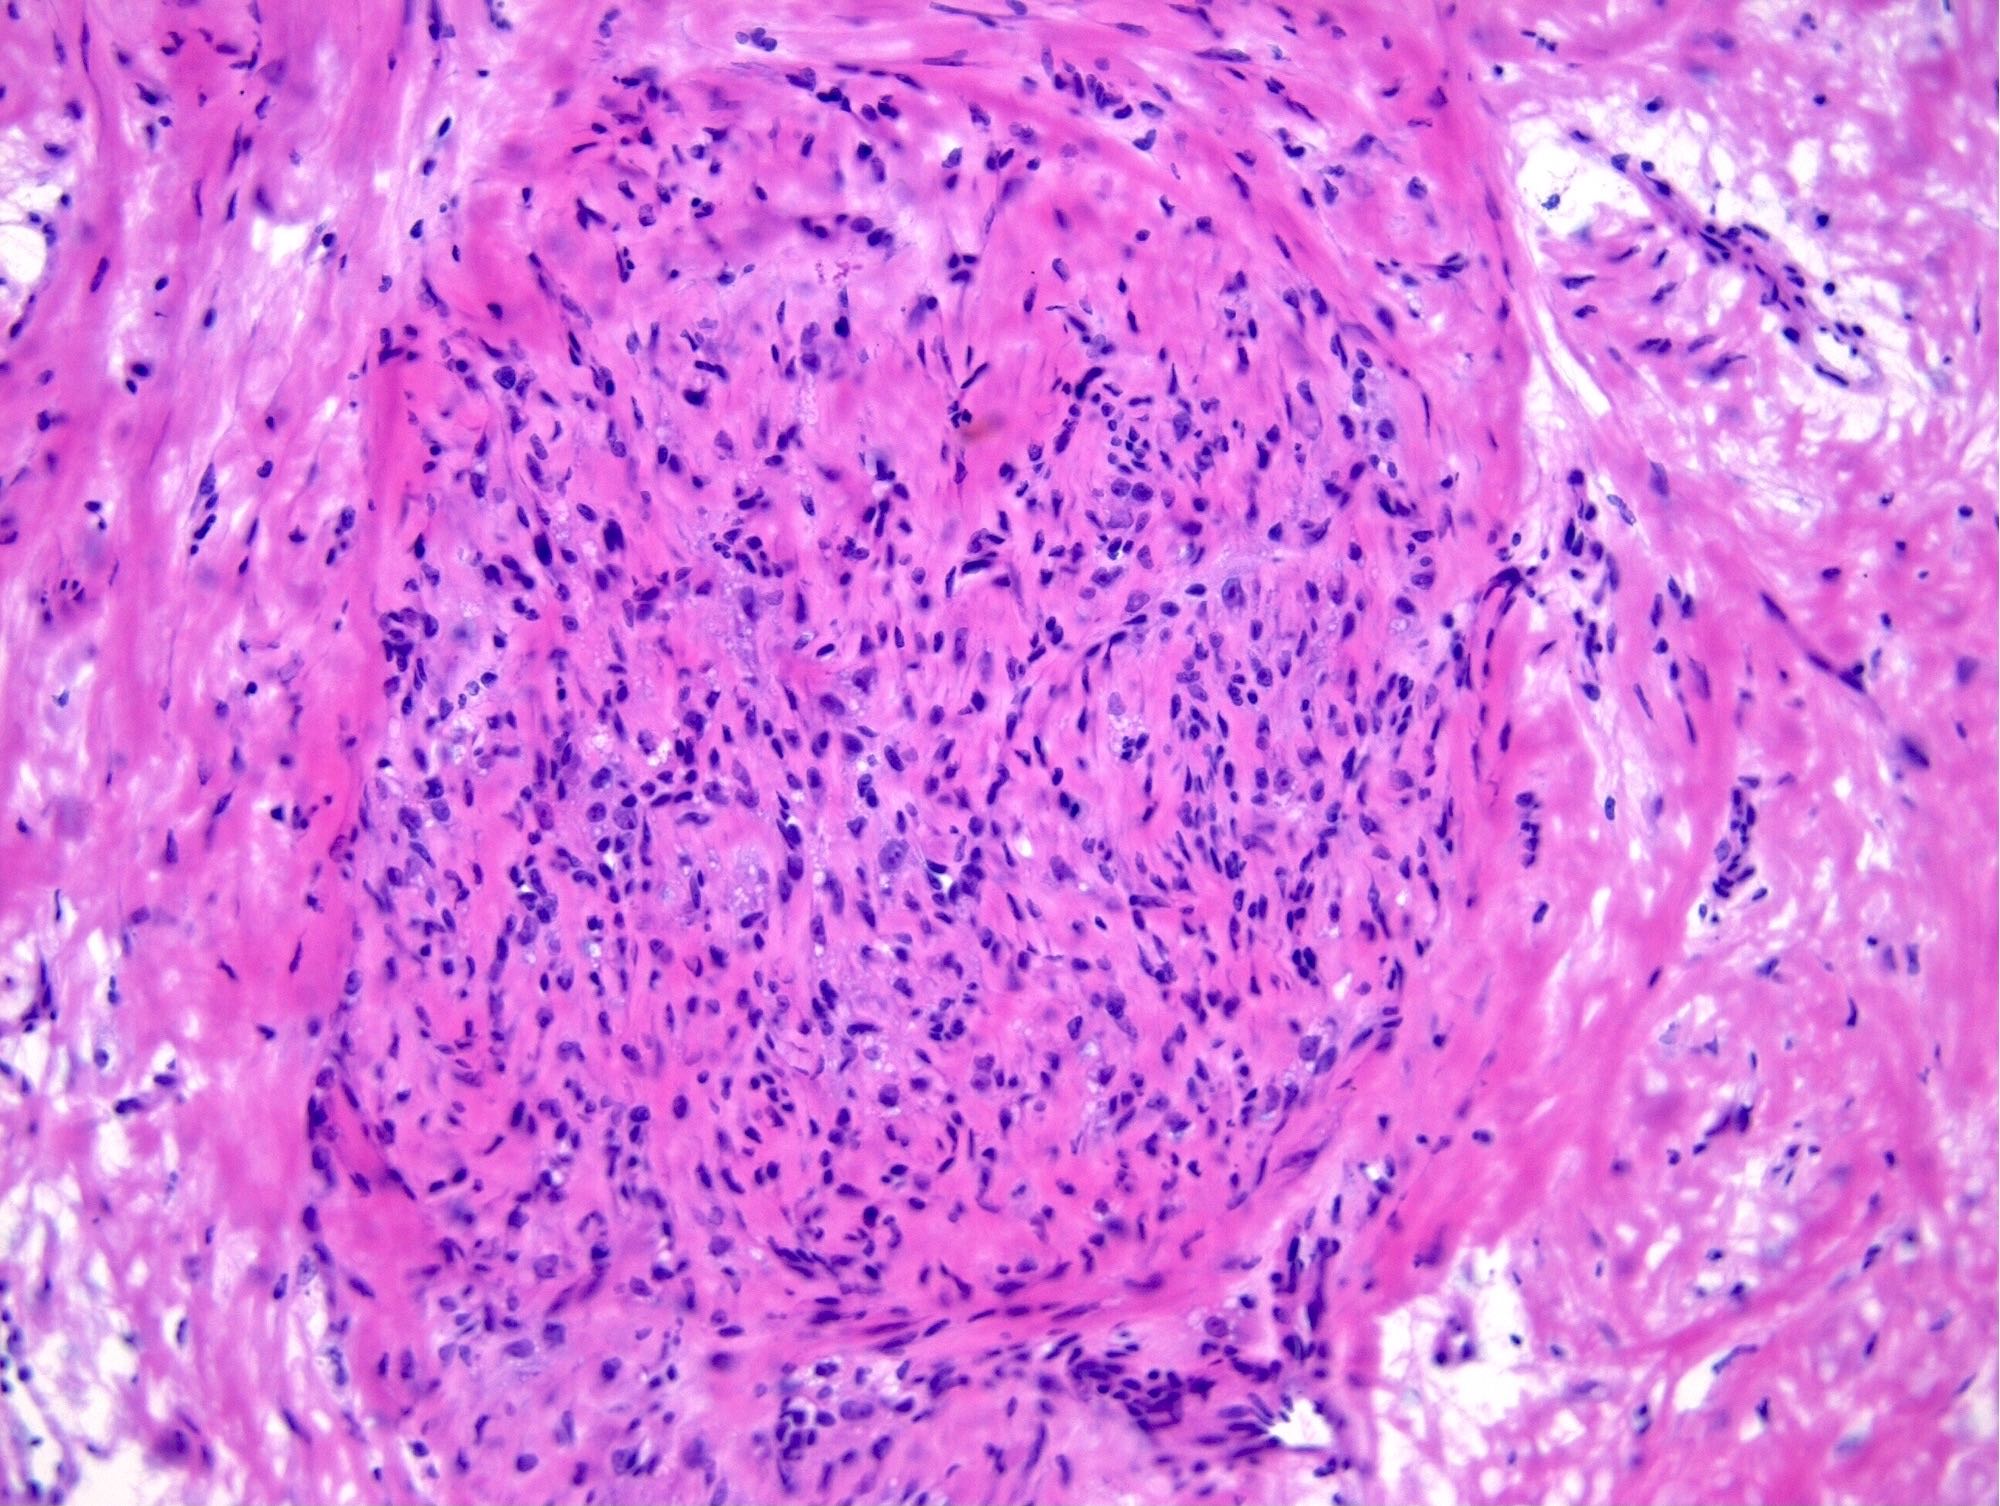

Microscopic (histologic) description

- Alternating cellular and hypocellular areas impart a pseudolobular appearance

- Thin, dilated and branching hemangiopericytoma-like vasculature is often conspicuous in both components

- Pseudolobules comprised of a jumbled admixture of epithelioid (lutein) and spindled cells with minimal atypia

- Epithelioid cells: round nuclei with prominent nucleoli, vesicular chromatin and clear to vacuolated cytoplasm

- Spindled cells: elongated nuclei with indistinct nucleoli, bland chromatin and scant eosinophilic cytoplasm

- Hypocellular areas can be edematous, collagenous (variably keloid-like) or myxoid